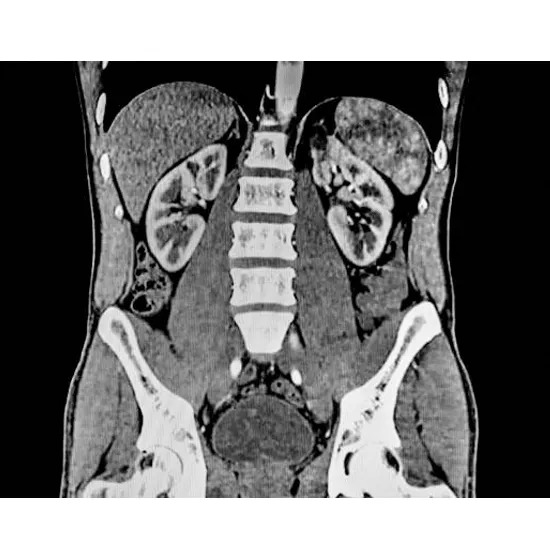

MRI abdomen imaging is one of the noninvasive radiographic tests. It helps to take a very clear picture of the upper section of the abdomen. It may help in imaging pictures of the gallbladder, liver, pancreas, and kidneys among other body parts. It can diagnose several conditions such as tumors, infections, and other structural anomalies. In some cases, the abdominal MRI with the contrast involves the administration of the contrast dye which will help to highlight details on blood vessels and the tenderness of the tissues. This scan type is devoid of radiation and, hence, relatively safer on the patient, it is also quite accurate regarding insight that might be put to use for treatment or diagnosis.

The scanning process for the upper abdomen under MRI involves a patient lying on a table that moves into the MRI machine. Also, if needed, contrast dye can be provided for better intensity of images. Strong magnetic fields and radio waves produce clear images of all abdominal organs in the machine. The time required might be between 30 to 60 minutes, on average, but the patient needs to remain as immobile as possible during the scan. Generally, the machine does produce quite loud noises, though earplugs or headphones are provided. After the scanning has taken place, a radiologist looks through the images created during the scan to see if there are any conditions or abnormalities present.

MRI scans of the upper abdomen have several very important benefits. They offer a good resolution of details and high-resolution images of main organs, like the liver, pancreas, kidneys, or gallbladder, with an accurate diagnosis for all complications such as tumors, infections, or structural anomalies. It is non-invasive and does not utilize any form of radiation; thus, it is relatively safer for patients. MRI abdomen with contrast will, therefore, amplify the definition of the images, particularly on the blood vessels and tissues. Since early detection leads to prompt guidance of effective treatment plans, this procedure may be repeated safely if called upon.